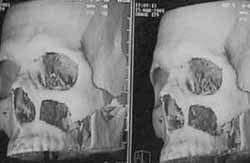

Se lleva a maxilectomía subtotal por “Degloving” (Figura 3), resecando sus paredes laterales, el nervio infraorbitario y parcialmente el piso de órbita, realizando etmoidectomía izquierda (Figura 4). Se realizó antrostomía intranasal y se dejó sonda de foley para hemostasia y soporte de piso de órbita. (Figuras 5A y 5B). Los controles postoperatorios descartan persistencia tumoral (Figura 6).

Reconstrucción tridimensional postoperatoriaFigura 6. Reconstrucción tridimensional postoperatoria.